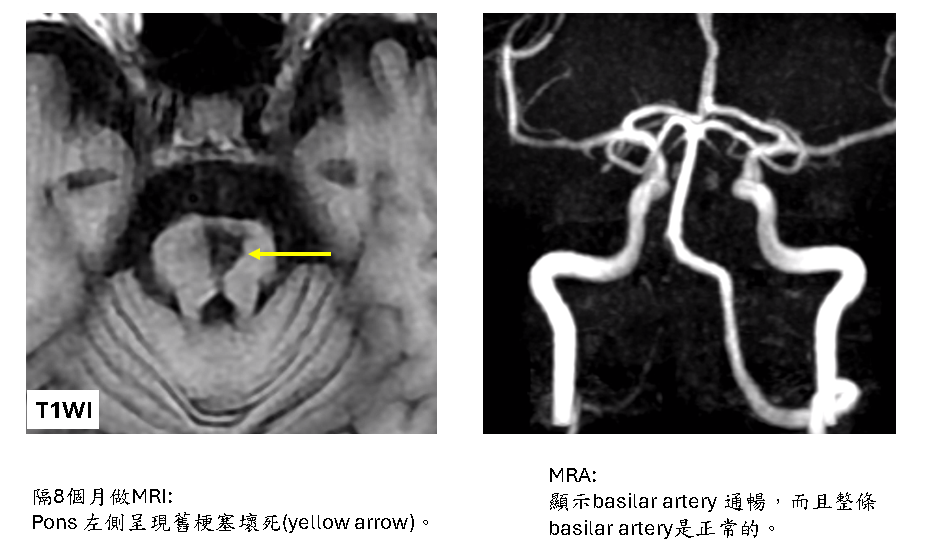

Acute pontine infarction, both sides of pons, with hemorrhagic transformation in left side, due to thrombosis in the parent artery (distal 1/2 of basilar artery )

這不是典型的pontine lacunar infarction due to small vessel disease.

這是pons的母血管basilar artery血栓(thrombus)堵住所引起,算是一種embolism (thromboembolism).

病患後來成為復健科長期患者,目前四肢仍無力 (肌力 4/5),走路不穩。